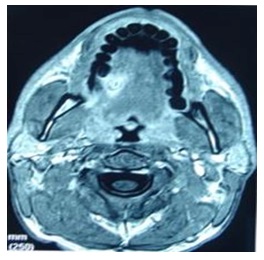

A thirty-year-old male without any previous medical history came to the accident and emergency department, at the General Hospital of the main city of this area. He complained of mouth pain. There was a large tuna fish bone on the mid right dorsal border of the tongue, which was removed. A few days later, he represented with a painful swelling of the tongue. A glossal abscess was aspirated with a large bore needle. An oral wide spectrum antibiotic and a non-steroidal anti inflammatory drug were prescribed. Two weeks later he returned with an increased tongue swelling without compromising the airway which showed a deep lesion in the lingual muscle (Figure 1&2) to the left of the midline Under general anaesthesia a wide incision of the lesion on the ventral tongue the direction of Wharton’s and further dissection of the former abscess opening. A silicone drain was left in place and the incision closed by three stitches. The patient improved a few hours after, and the episode resolved completely without any further complications (Figure 3&4).

Figure 1

Figure 1: Nuclear Magnetic resonance of the lesion in the right sided tongue.

Figure 2

Figure 2: More posterior imagine of the lesion.